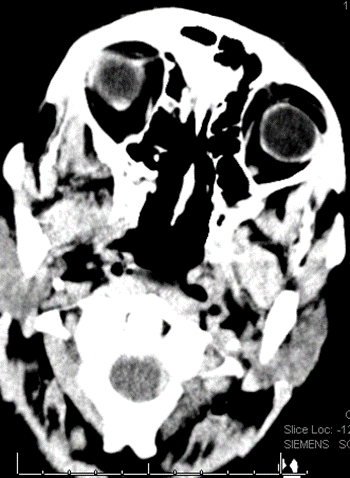

4/ All the ventricles are enlarged. There is some degree of transependymal flow with sulcal effacement, so unlikely this is NPH. Most likely communicating π§ π§. But why?

5/ Remember a colloid cyst will give you obstructive π§ π§. Patient without history of cancer, but cannot rule out, so vast differential. Do you LP?